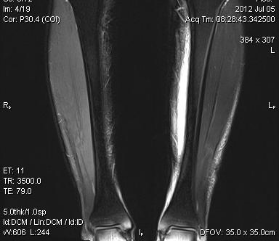

典型病例:患者,男,40岁,体能训练致左小腿肌肉撕裂伤并巨大血肿,给予脉冲磁疗、中频电疗和下肢肌肉训练指导后,血肿逐渐消退,两个月后肌肉恢复正常,继续参加训练。